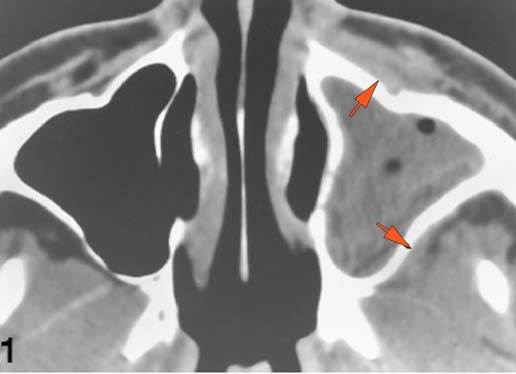

There is bone erosion along the walls of any affected sinuses. |

Yes | NA |

The extraconal orbital fat is abnormal. |

There is a subperiosteal abscess or edema along the medial wall, roof or floor of the orbit. |

There is bone erosion along the walls of the orbit. |

Findings are consistent with the clinical diagnosis of acute or subacute sinusitis superimposed on chronic mucocele with intracranial complications of epidural empyema along the orbital roof and early frontal lobe cerebritis.